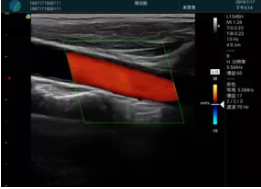

可視化甲狀腺穿刺引導(dǎo)

頸動脈血流充盈飽滿,無外溢